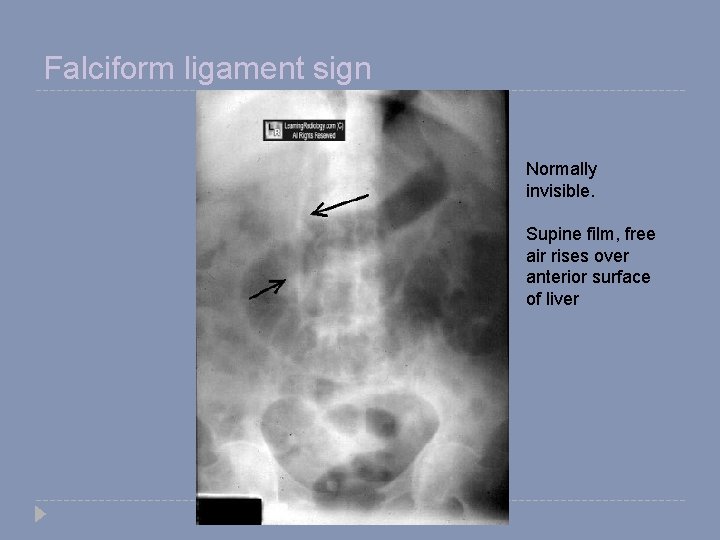

Signs of free air � Crescent sign � Riglers sign � Football sign � Falciform ligament sign

Falciform ligament sign Normally invisible. Supine film, free air rises over anterior surface of liver